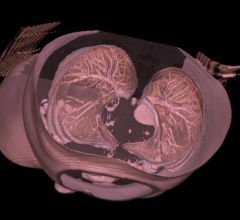

Feature | Sabah Servaes, M.D., and Sjirk J. Westra

Imaging children has challenges that relate to the size, maturity and anxiety of the patient. In addition, we have…

Feature | Dave Fornell

New computed tomography (CT) dose studies and growing public media attention have made minimizing unnecessary radiation…